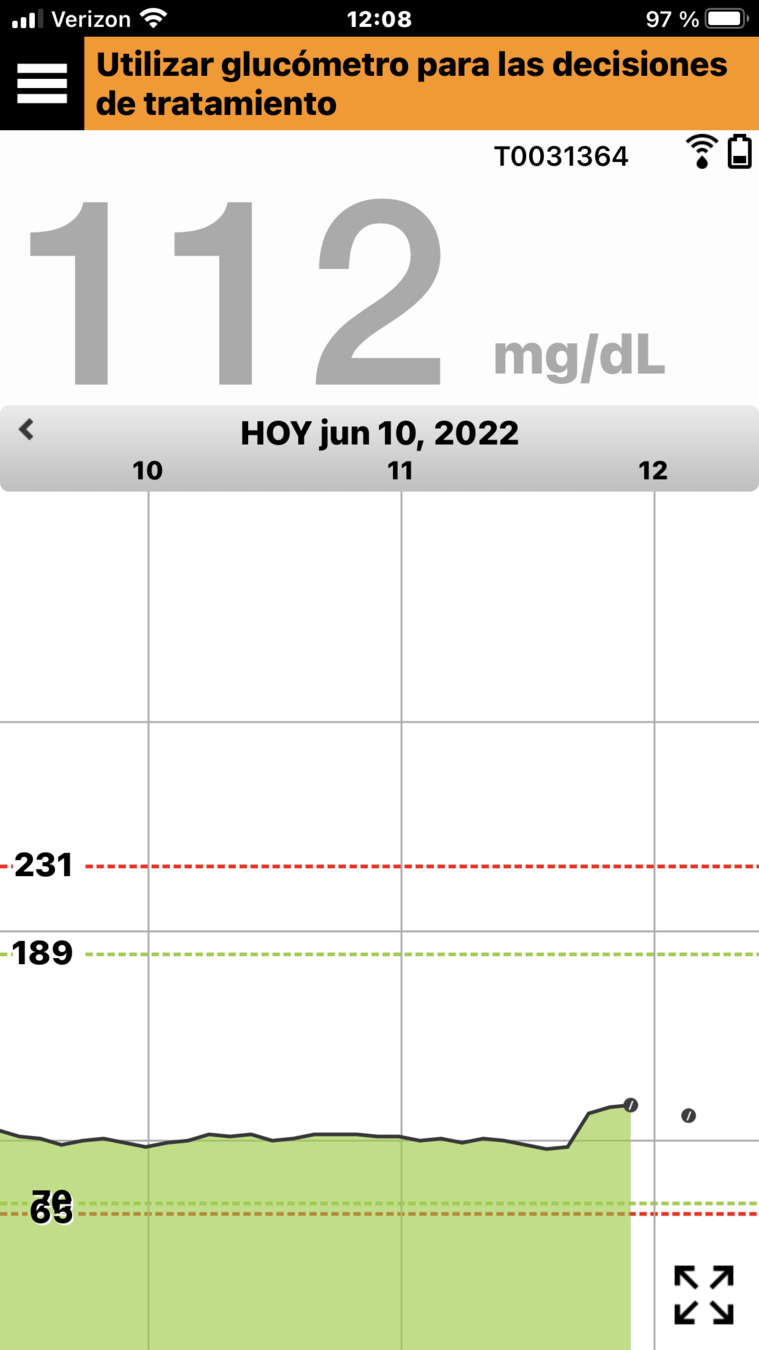

Y, en la parte inferior, se encuentra el gráfico de tendencia de la glucosa.

Las líneas discontinuas rojas indican los niveles de alerta de glucosa alta y baja, y las líneas discontinuas verdes indican el intervalo objetivo.

Todos los eventos que introduzca en la aplicación (como una calibración, comida, ejercicio

o insulina) o las alertas que reciba, se mostrarán en el gráfico de tendencia con un icono.

Al igual que con todos los sistemas de MCG, hay ocasiones en las que debe utilizar el valor de un medidor de glucosa en sangre en lugar de su sistema de MCG Eversense® E3 para tomar una decisión sobre el control o tratamiento de la diabetes.

CUÁNDO USAR EL MEDIDOR DE GLUCOSA EN SANGRE

Si sus síntomas no coinciden con el valor de glucosa del sensor.

Cuando no se muestra el valor de glucosa o flecha de tendencia.

Cuando la barra de estado de la aplicación Eversense® indica “Utilice el medidor de glucosa en sangre para decisiones del tratamiento”.

Si está usando un antibiótico de la clase de las tetraciclinas, ya que esta clase de fármacos puede provocar un falso descenso de los valores de glucosa del sensor.

CUÁNDO USAR EL MEDIDOR DE GLUCOSA EN SANGRE